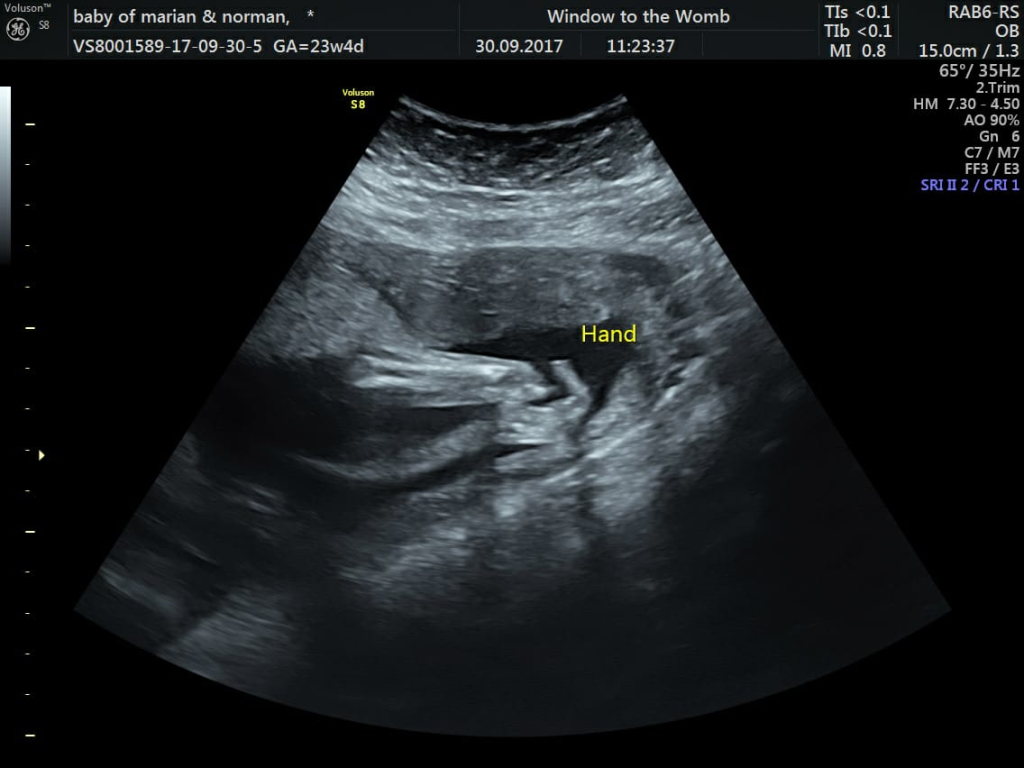

Parents Marian and Norman attended their 20-week scan at the hospital to unsuspectingly find concerns with baby Jacks’ heart. After returning for another scan at 23 weeks, they couldn’t get the view of Jacks’ heart they needed…but discovered an absent left hand. Marian had planned to visit us at Window to the Womb for a scan at 28 weeks, but after discovering the possible heart issues, decided they needed reassurance as soon as possible. They joined us 3 days later, mainly to see if baby was okay through our technology.

Baby Jacks’ 4D Scan at 23 Weeks

“We really are thankful of your team in Belfast as what was the most concerning days; the scan with WTTW gave me a little hope. When I was told about the absent left hand at 23 weeks I went onto shock as I thought the man had got it wrong. But 2 days later and 2 days of thinking, then seeing the baby 4D put my mind at ease.” – Marian B.

Marian got in touch recently and gave us the wonderful news…the heart consultant had given Jack the all clear at 28 weeks! He was born happy and healthy on the 17th January, weighing 7lbs 4 oz. Although his left hand is absent, he is missing less than expected with more of a wrist; this means he will have more support.

After learning more at the children’s hospital, his missing hand is the best out of a challenging situation, and they’re “just thankful he is perfect”. Mummy has told us that Jack is thriving and will be 6 weeks old soon. We are all so thankful Jack and family are well. His 8 year old brother Ollie is especially over the moon and he’s looking forward to playing football with him!